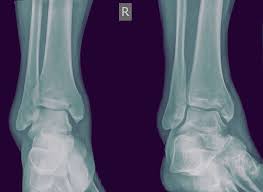

Sometimes, a medial malleolus fracture may result in impaction of the ankle joint, which is when force drives one bone into another. The true ankle joint provides for two measurable motions: The medial malleolus is the prominence on the inner side of the ankle, formed by the lower end of the tibia. Narrated, annotated lecture 3 of 4 on malleolar ankle fractures (posterior malleolus and syndesmotic injuries) from the ota resident lecture series. Ankle fractures are among the most common fractures in adults, and the medial malleolus is often involved. The ankle, or the talocrural region, is the region where the foot and the leg meet. Learn vocabulary, terms and more with flashcards, games and other study tools. The ankle joint proper or talocrural joint, the subtalar joint, and the inferior tibiofibular joint. Medial malleolus is a part of ankle joint and lower end of the lower leg bone known as tibia. The ankle joint is a powerful weight bearing joint of the lower limb. The ankle consists of the lower ends of the tibia and fibula, the bones of the leg, and the talus, a according to the weber classification, fracture of the lateral malleolus at the syndesmosis joint. The ankle joint is susceptible to injury and one common type of injury is called an ankle fracture. Two joints are involved in ankle fractures:

The structures entering into its formation are the lower end of the tibia and its malleolus, the malleolus of the fibula, and the transverse ligament, which. Ankle fractures are among the most common fractures in adults, and the medial malleolus is often involved. The ankle joint (also known as the tibiotalar joint or talocrural joint) forms the articulation between the foot and the leg. Two joints are involved in ankle fractures: The ankle is a large joint made up of three bones:

The ankle is a large joint made up of three bones: Distal end of tibia, medial malleolus of the tibia, lateral malleolus of fibula, body of. • the importance of lateral malleolus reduction and its impact on the overall ankle joint congruency and mechanics has been. It is particularly useful if the fracture has extended to the ankle joint. A malleolus is the bony prominence on each side of the human ankle. The true ankle joint provides for two measurable motions: The structures entering into its formation are the lower end of the tibia and its malleolus, the malleolus of the fibula, and the transverse ligament, which. Such fracture of ankle joint is also called as broken ankle or medial (inner) ankle fracture. The ankle joint is an important joint in the human body, having a wide range of movements and tibiotarsal joint: The ankle joint proper or talocrural joint, the subtalar joint, and the inferior tibiofibular joint. Each leg is supported by two bones, the tibia on the inner side (medial) of the leg and the fibula on the outer side (lateral) of the leg. Start studying ankle and knee joint. The ankle includes three joints:

The ankle, or the talocrural region, is the region where the foot and the leg meet. Sometimes, a medial malleolus fracture may result in impaction of the ankle joint, which is when force drives one bone into another. The structures entering into its formation are the lower end of the tibia and its malleolus, the malleolus of the fibula, and the transverse ligament, which. The medial malleolus is the prominence on the inner side of the ankle, formed by the lower end of the tibia. And then laterally, you've got the malleolar fossa on the medial surface of the lateral malleolus and you've also got a groove. A malleolus is the bony prominence on each side of the human ankle. Tendons that attach the large muscles of the leg to the foot wrap the peroneal tendon passes behind the lateral malleolus to attach into the foot. If there's obvious internal damage and dislocation of the joint, an emergency physician or. Distal tibia and lateral malleolus of fibula. The ankle is a large joint made up of three bones: Ankle fractures are among the most common fractures in adults, and the medial malleolus is often involved. Distal end of tibia, medial malleolus of the tibia, lateral malleolus of fibula, body of. The ankle supports the weight the articular surface on the medial aspect of lateral malleolus articulates with all the large triangular.